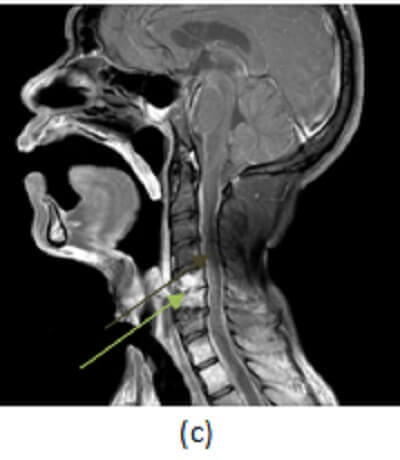

Figure 1: (a, red arrow) T1 sagittal images of the cervical spine demonstrate low T1 signal involving the C5-6 vertebra and replacement of the normal cervical ventral epidural fat signal with low T1 soft tissue (purple arrow). (b, blue arrow) T2 fat saturated images (to cancel out the background fatty marrow signal in the vertebra) show increased T2 signal involving the C5-6 vertebra and disc space most consistent with edema. (c, green arrow) T1 post contrast with fat saturation demonstrates enhancement of the C5-6 vertebra and disc along with enhancement of the ventral epidural space (brown arrow).